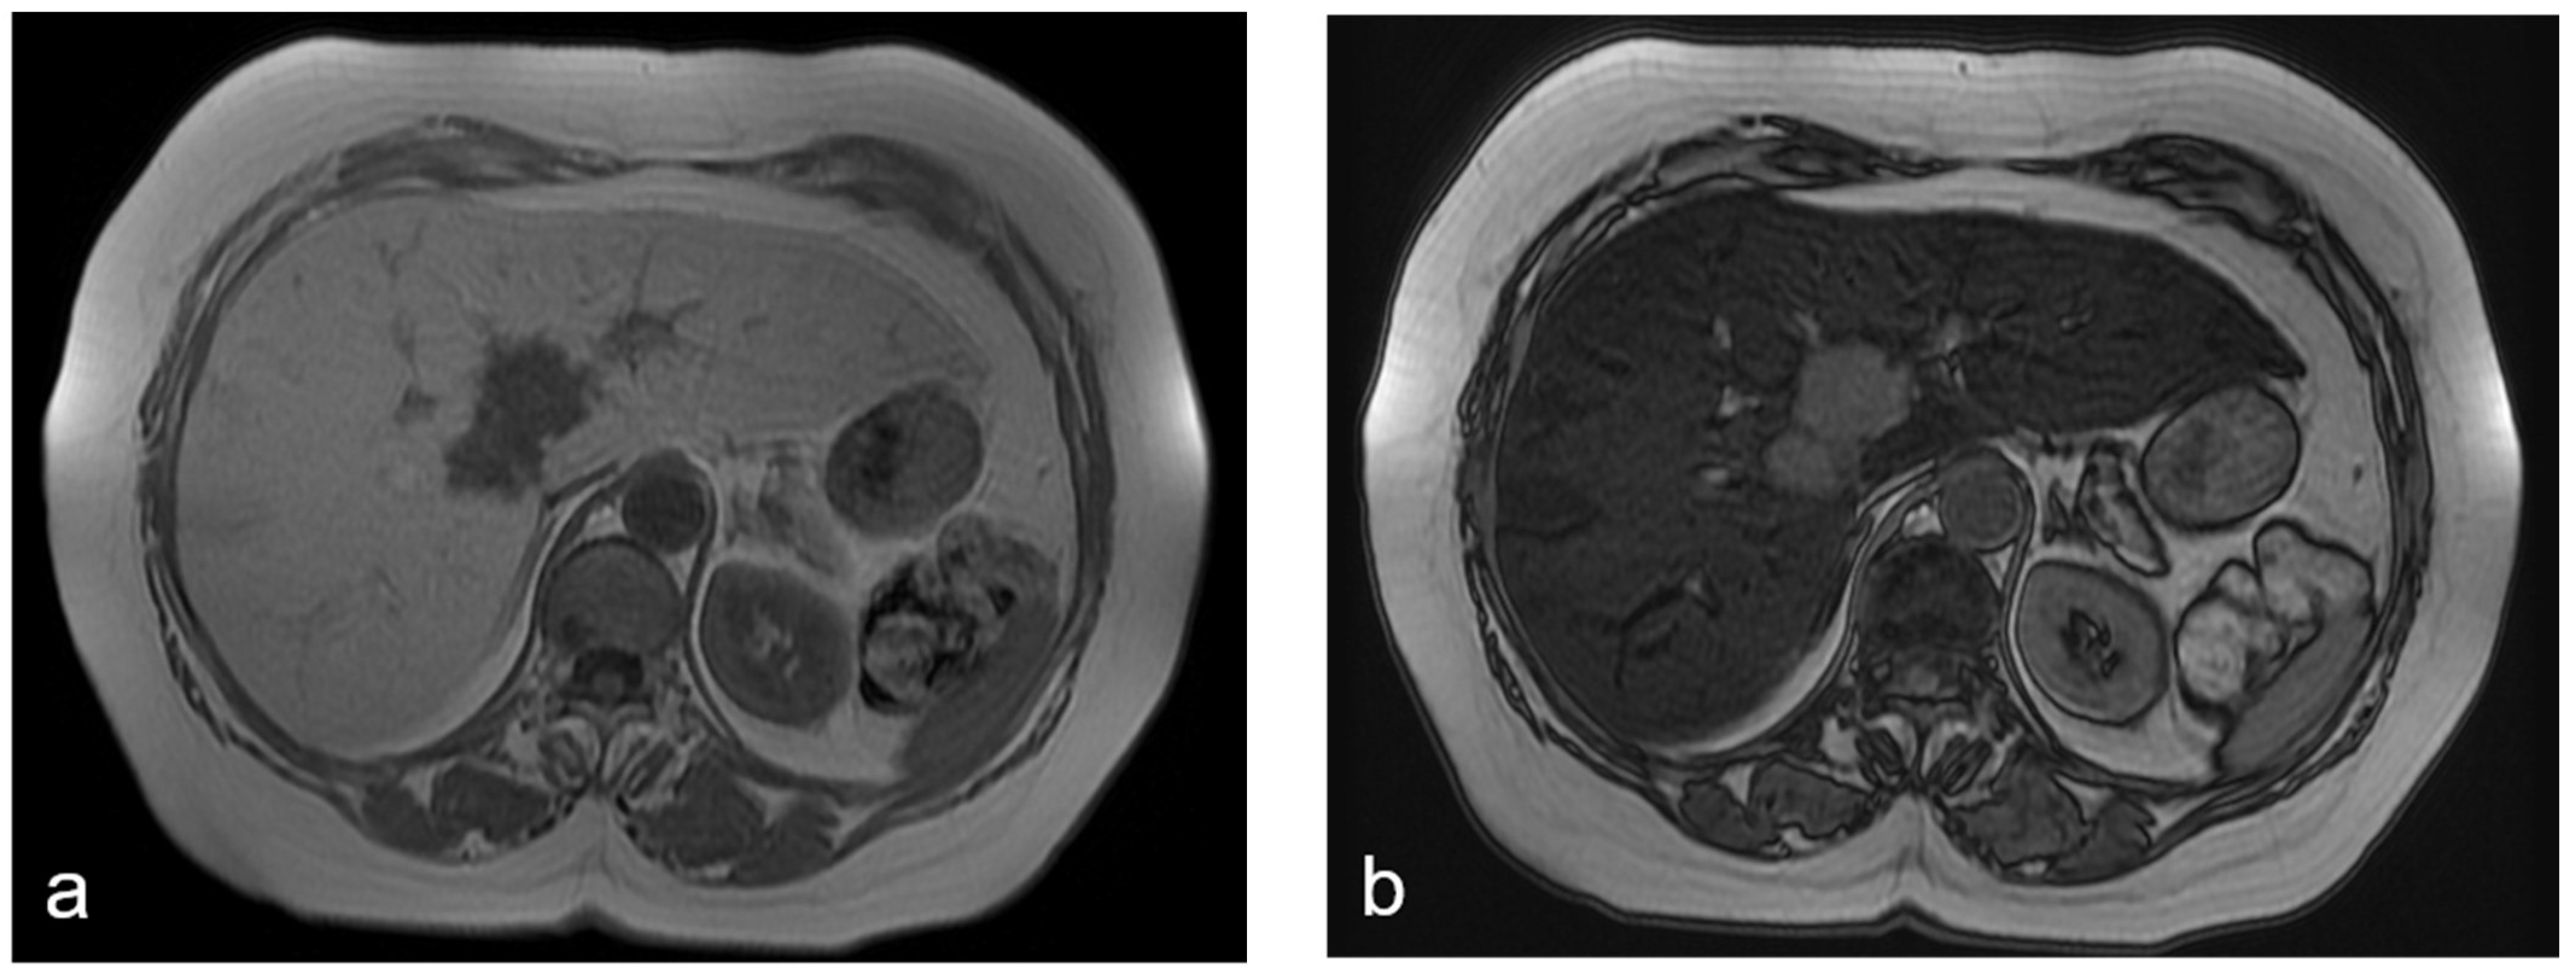

2. Hepatic Steatosis, Steatohepatitis, and Cirrhosis

- Vernuccio, F.; Dioguardi Burgio, M.; Barbiera, F.; Cusmà, S.; Badalamenti, G.; Midiri, M.; Vilgrain, V.; Brancatelli, G. CT and MR imaging of chemotherapy-induced hepatopathy. Abdom. Radiol. 2019, 44, 3312–3324. [Google Scholar] [CrossRef]

- Jang, J.K.; Jang, H.; Kim, J.S.; Kim, T.K. Focal fat deposition in the liver: Diagnostic challenges on imaging. Abdom. Radiol. 2017, 42, 1667–1678. [Google Scholar] [CrossRef]

- You, S.; Park, B.J.; Kim, Y.H. Hepatic lesions that mimic metastasis on radiological imaging during chemotherapy for gastrointestinal malignancy. Korean J. Radiol. 2017, 18, 413–426. [Google Scholar] [CrossRef]